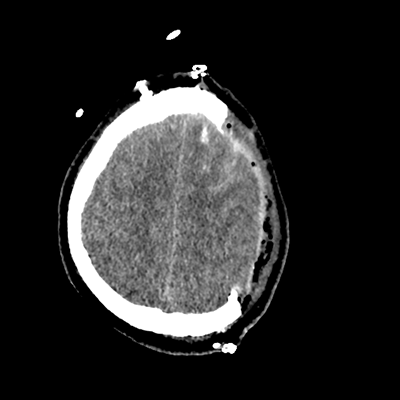

On day 5 of admission, he begins having intracranial hypertension again, spiking up to 40mmHg. You bolus with propofol and fentanyl, to no avail. You then push 30mL of 23.4% NaCl, which provides some brief improvement, allowing you to quickly get a non-contrast head CT. Unfortunately, he's now back up to 36mmHg. You review his labs, and note the following: Na 150, K 3.8, Cl 119, HCO3 18, BUN 21, Cr 0.85, glucose 136, sOsm 320.

NCHCT

NCHCT 2/20 2/20